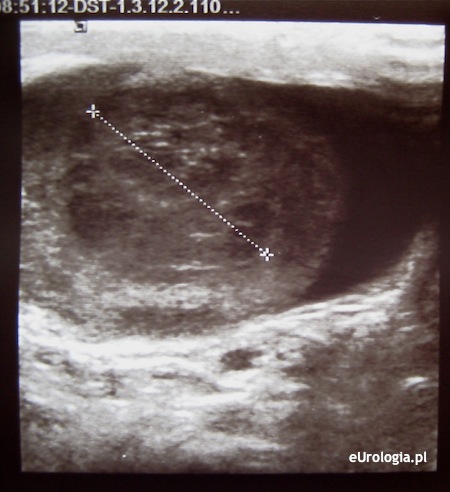

Badanie USG moszny jest podstawowym badaniem obrazowym w diagnostyce obrazowej schorzeń jąder. Rozpoznanie różnicowe zapalenia jądra i guza jądra jest z reguły proste i nie sprawia problemów diagnostycznych. Brak efektu po leczeniu antybiotykiem i niejasny obraz kliniczny jest wskazaniem do konsultacji urologicznej.

Fot. Guz jądra - obraz w USG.